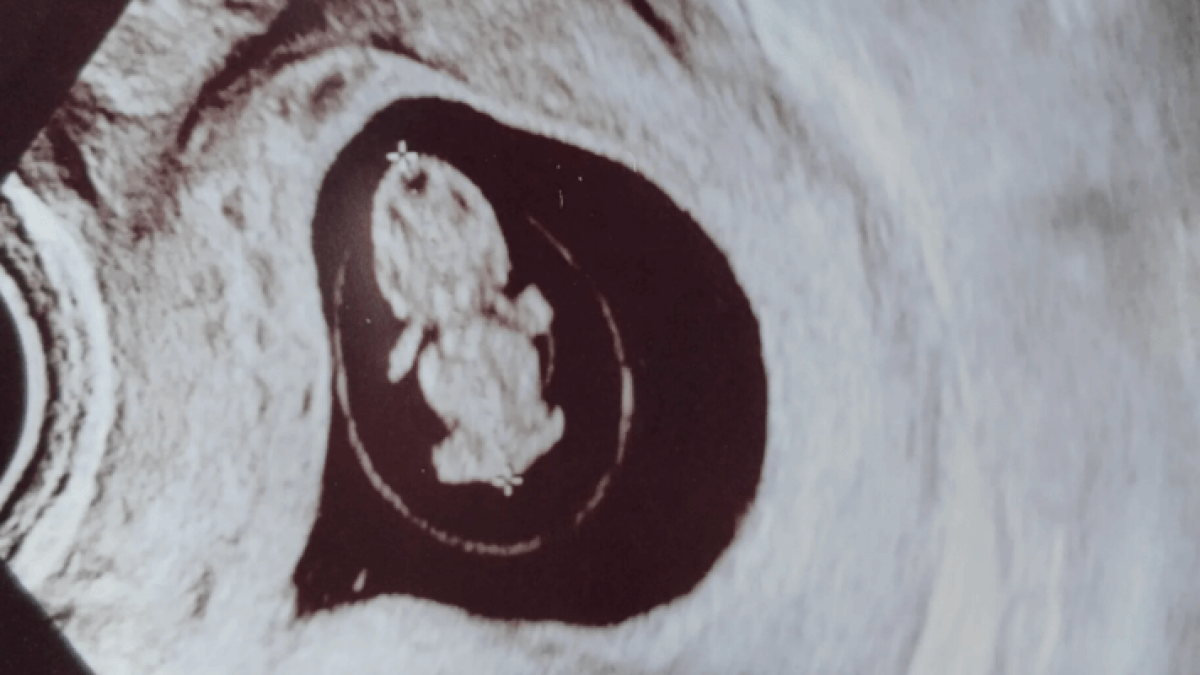

Muistan kuinka puhelinlangan toisessa päässä naistenpolilla oli syvä hiljaisuus kun soitin ja esitin asiani. Vastaanotolla lääkäri puhui meille rauhallisesti, ammattimaisesti, mutta jokainen sana putosi raskaana lattialle kuin kivi veteen. “Raskaus on todettu ja se on täysin normaali. Viikkoja 9+5.”

Ja niin se teki tälläkin kertaa. Raskausviikolla 12+2 ultrassa todettiin että raskaus keskeytetään. Lapsi oli kiinnittynyt kohdussa aivan vasempaan reunaan osin niin hankalasti, ettei raskauden jatkaminen ollut mahdollista. Luulin että lääkärin sanat " teidän päätöksellä ei ole enää mitään väliä, vaan meidän täytyy päättää teidän puolesta" olisi ollut lohdullinen ja helpottava asia, mutta ei se toiminut niin. Tuli ilmi, että myöskään raskauden keskeytys ei ollut mahdollista. Molemmissa lopputuloksina se, että komplikaationa kohtuni ja munatorvi räjähtää ja lopputuloksena sisäinen verenvuoto. Taas kerran keskusteltiin omasta eloonjäämisestä. Tässä kohtaa kaiken sen kriisin keskellä kävin läpi magneettikuvia, tutkimuksia ja konsultaatioita.